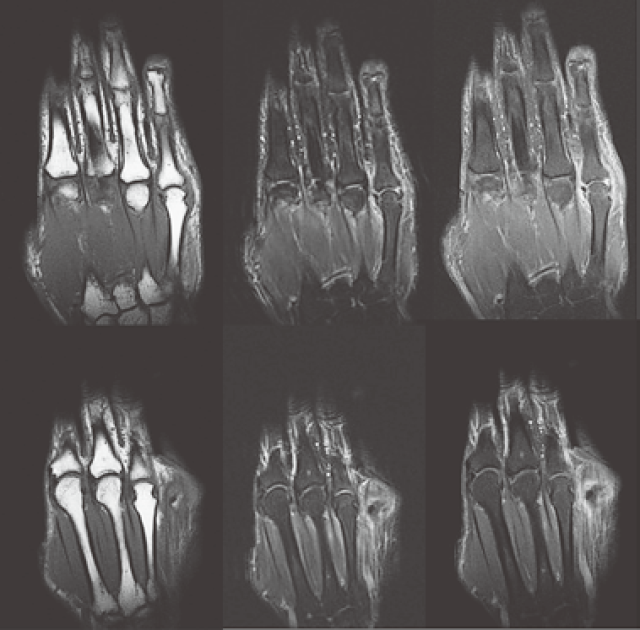

莆田回春堂类风湿关节炎导致的十种手脚部畸形

鹅颈畸形